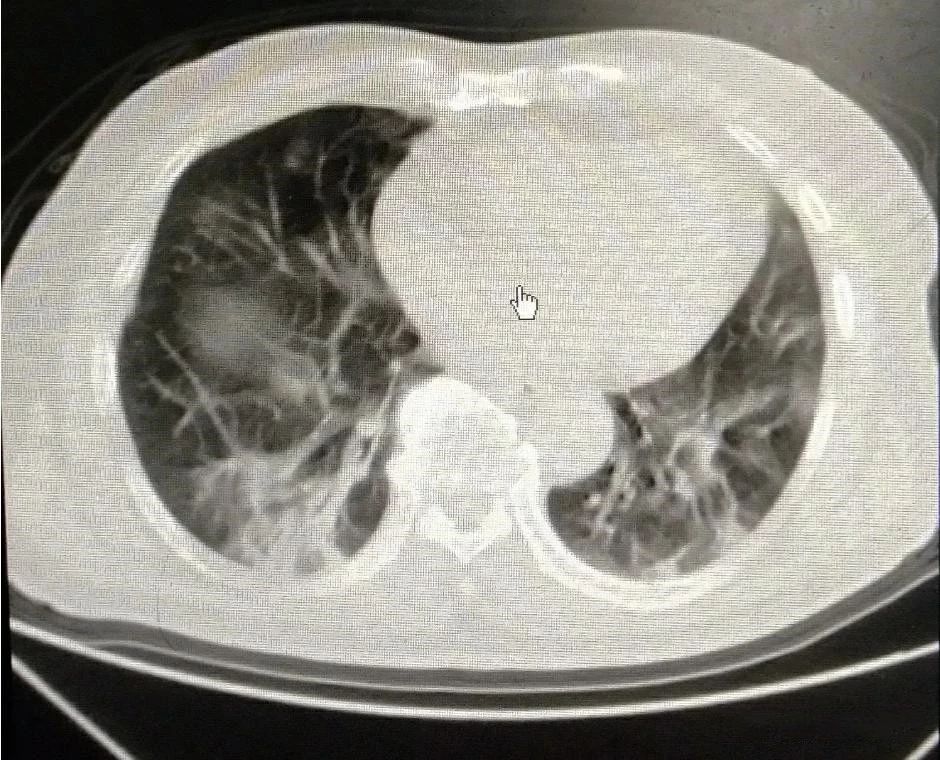

下图是同一位患者三次CT检查的图像,每次检查相隔2天,我们来看看肺部的变化。

大家可以很清楚地看到,右侧(患者的左胸)肺部全变白了,左侧(患者右胸)变白的面积也是非常大。

正常的肺组织里含有大量的空气,对X线的阻挡能力很弱,所以在X线下呈现黑色。当肺部出现炎症反应,大量蛋白、组织液、白细胞等渗出,肺间质充血、水肿等,这时的肺组织对X线的吸收能力就明显增强了,有点像实质器官的表现,所以呈现出白色。

变成白色的肺组织,基本上失去了气体交换的能力,患者会感到明显的缺氧,呼吸困难。我们需要给患者吸氧,重症者上呼吸机,甚至动用ECMO进行治疗。上面我举例的这位患者,就是一位新型冠状病毒感染的患者,最终由于病情发展太快,而不幸死亡。